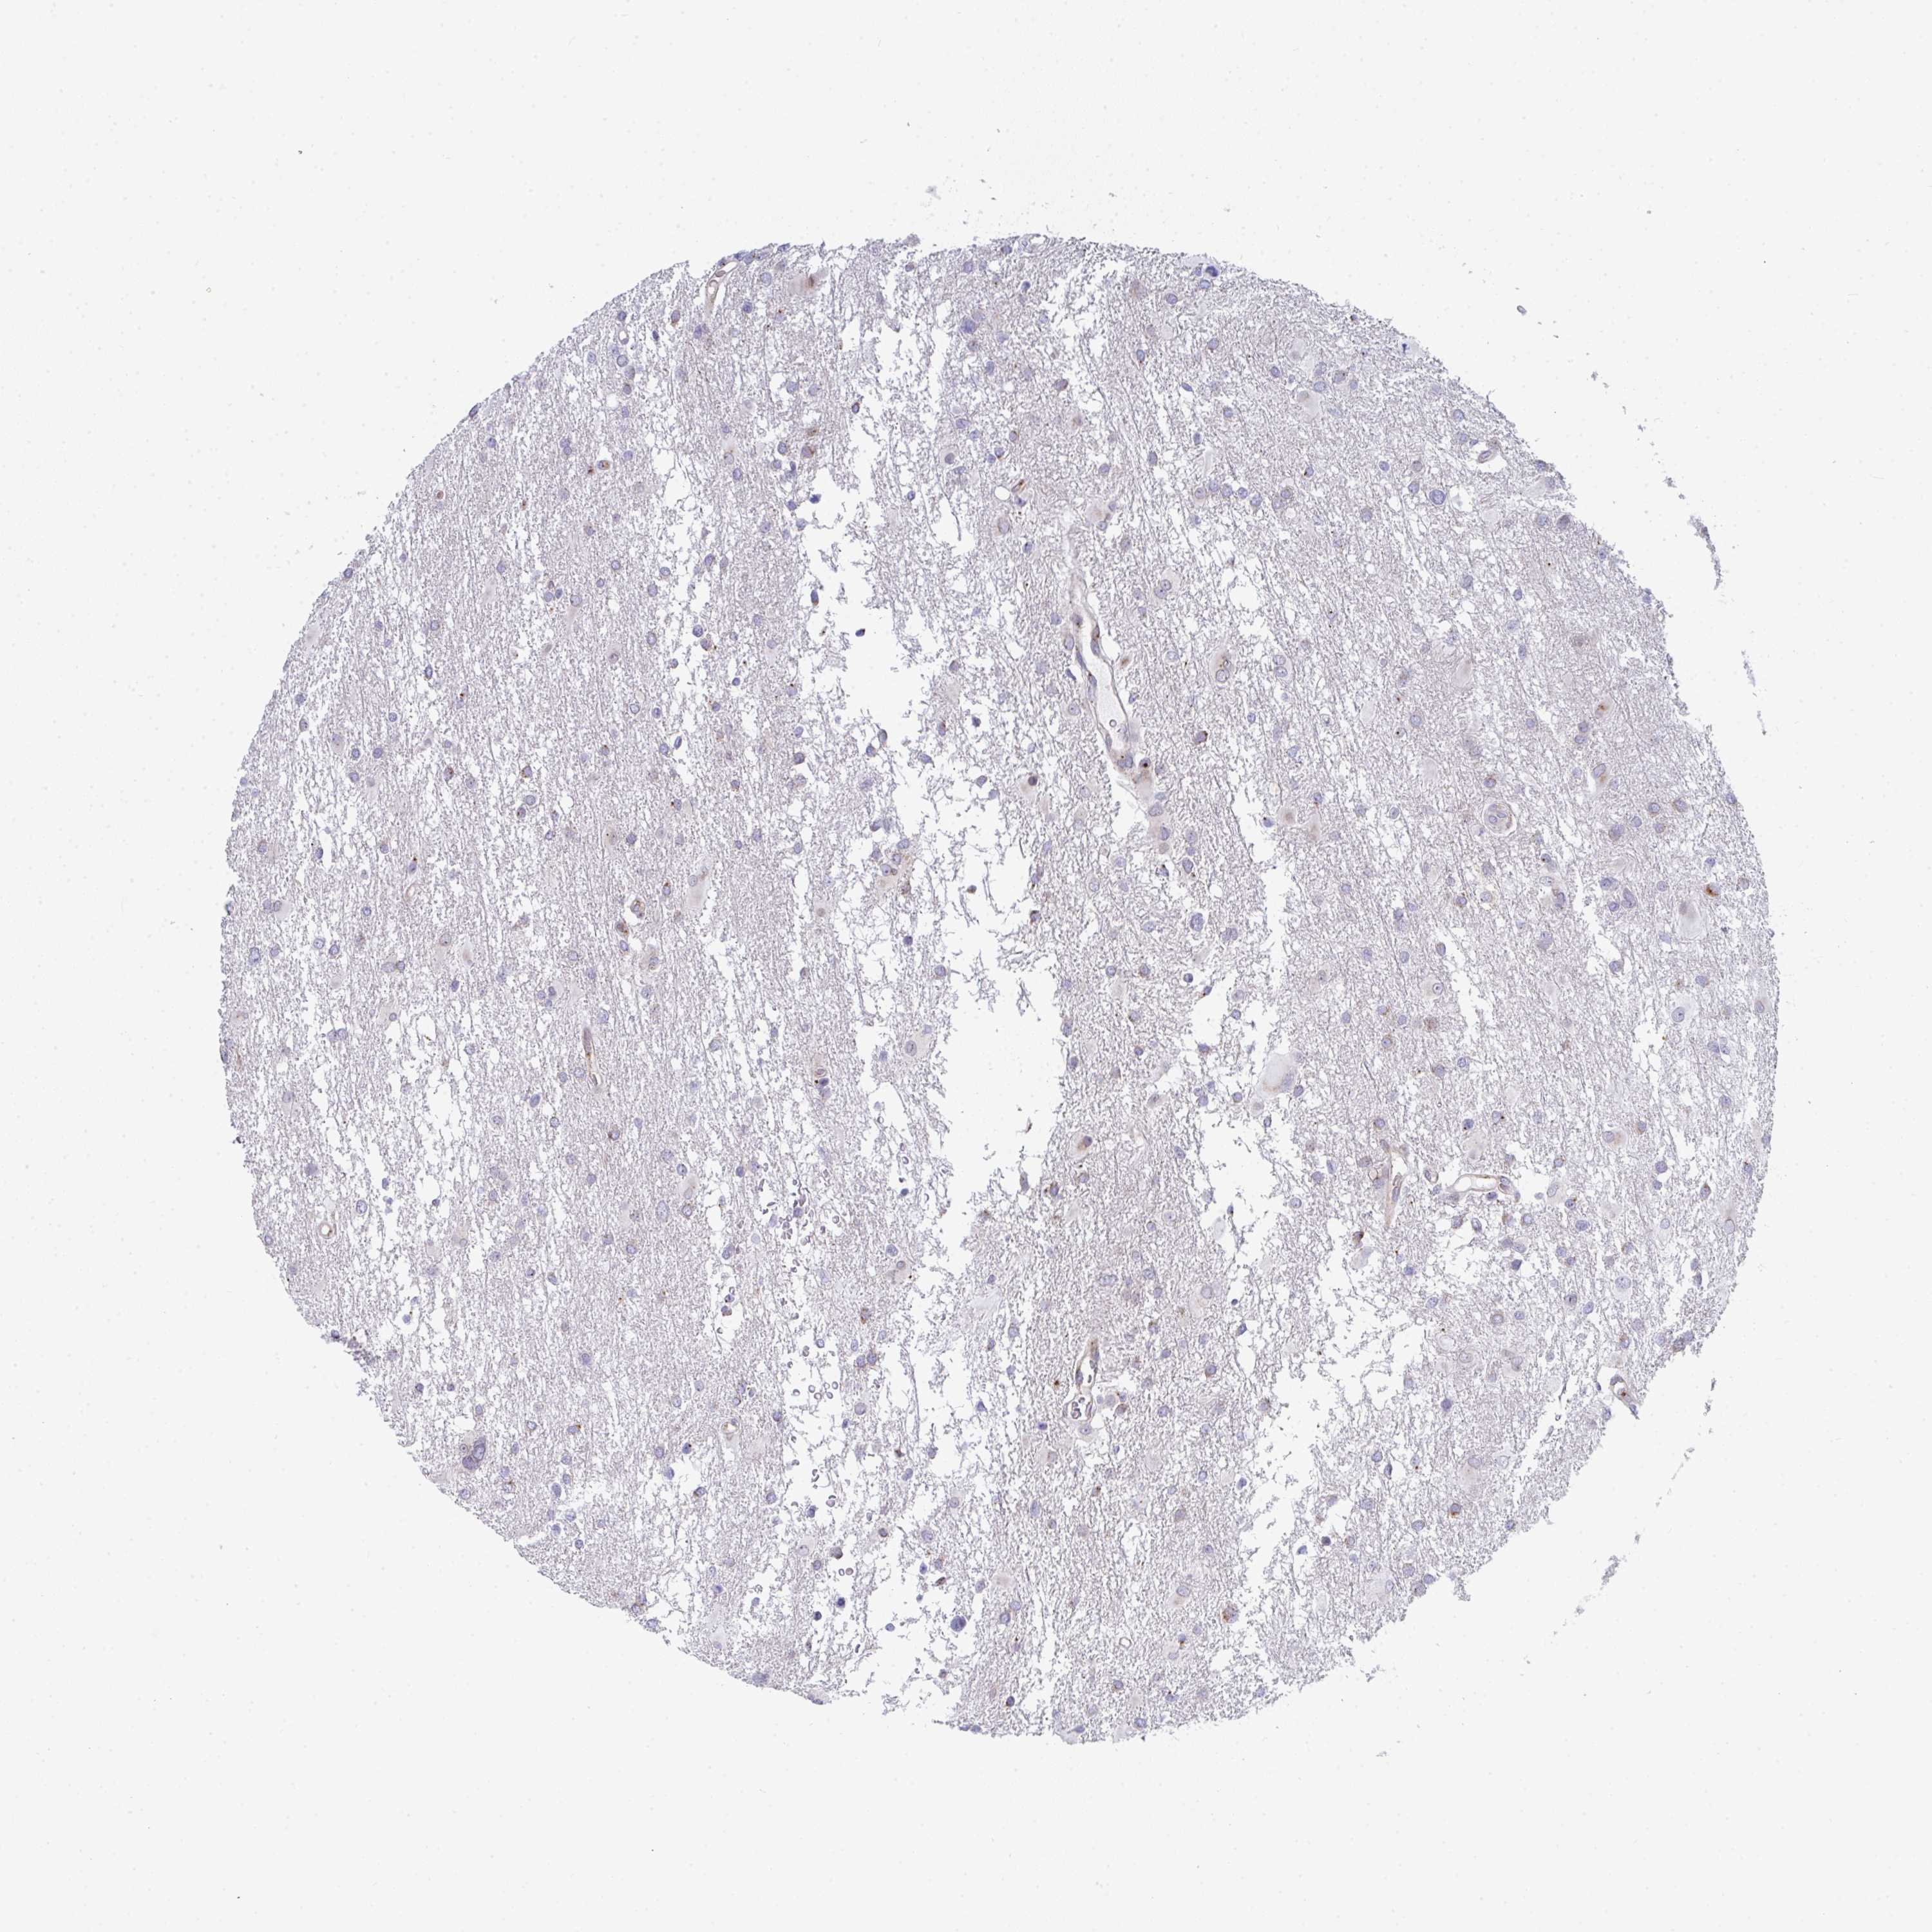

GLIOMA - Protein expressioni

A mouse-over function shows sample information and annotation data. Click on an image to view it in a full screen mode. Samples can be filtered based on level of antibody staining by selecting one or several of the following categories: high, medium, low and not detected. The assay and annotation is described here.

Note that samples used for immunohistochemistry by the Human Protein Atlas do not correspond to samples in the TCGA dataset.

Antibody stainingi

Antibody staining in the annotated cell types in the current human tissue is reported as not detected, low, medium, or high, based on conventional immunohistochemistry profiling in selected tissues. This score is based on the combination of the staining intensity and fraction of stained cells.

Each image is clickable and will lead to virtual microscopy that enables deeper exploration of all samples and also displays staining intensity scores, fraction scores and subcellular localization as well as patient and tissue information for each sample.

Antibody HPA026294

Antibody HPA053709

Staining

High

Medium

Low

Not detected

Intensity

Strong

Moderate

Weak

Negative

Quantity

>75%

75%-25%

<25%

None

Location

Nuclear

Cytoplasmic/membranous

Cytoplasmic/membranous,nuclear

Glioma, malignant, High grade

Glioma, malignant, Low grade

Glioblastoma, NOS